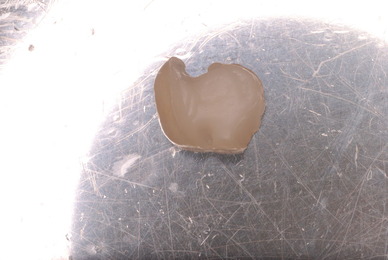

![10603456_965331023543550_8605764471775043725_n[1]](https://livedoor.blogimg.jp/netdental/imgs/a/5/a5deb28d-s.jpg)